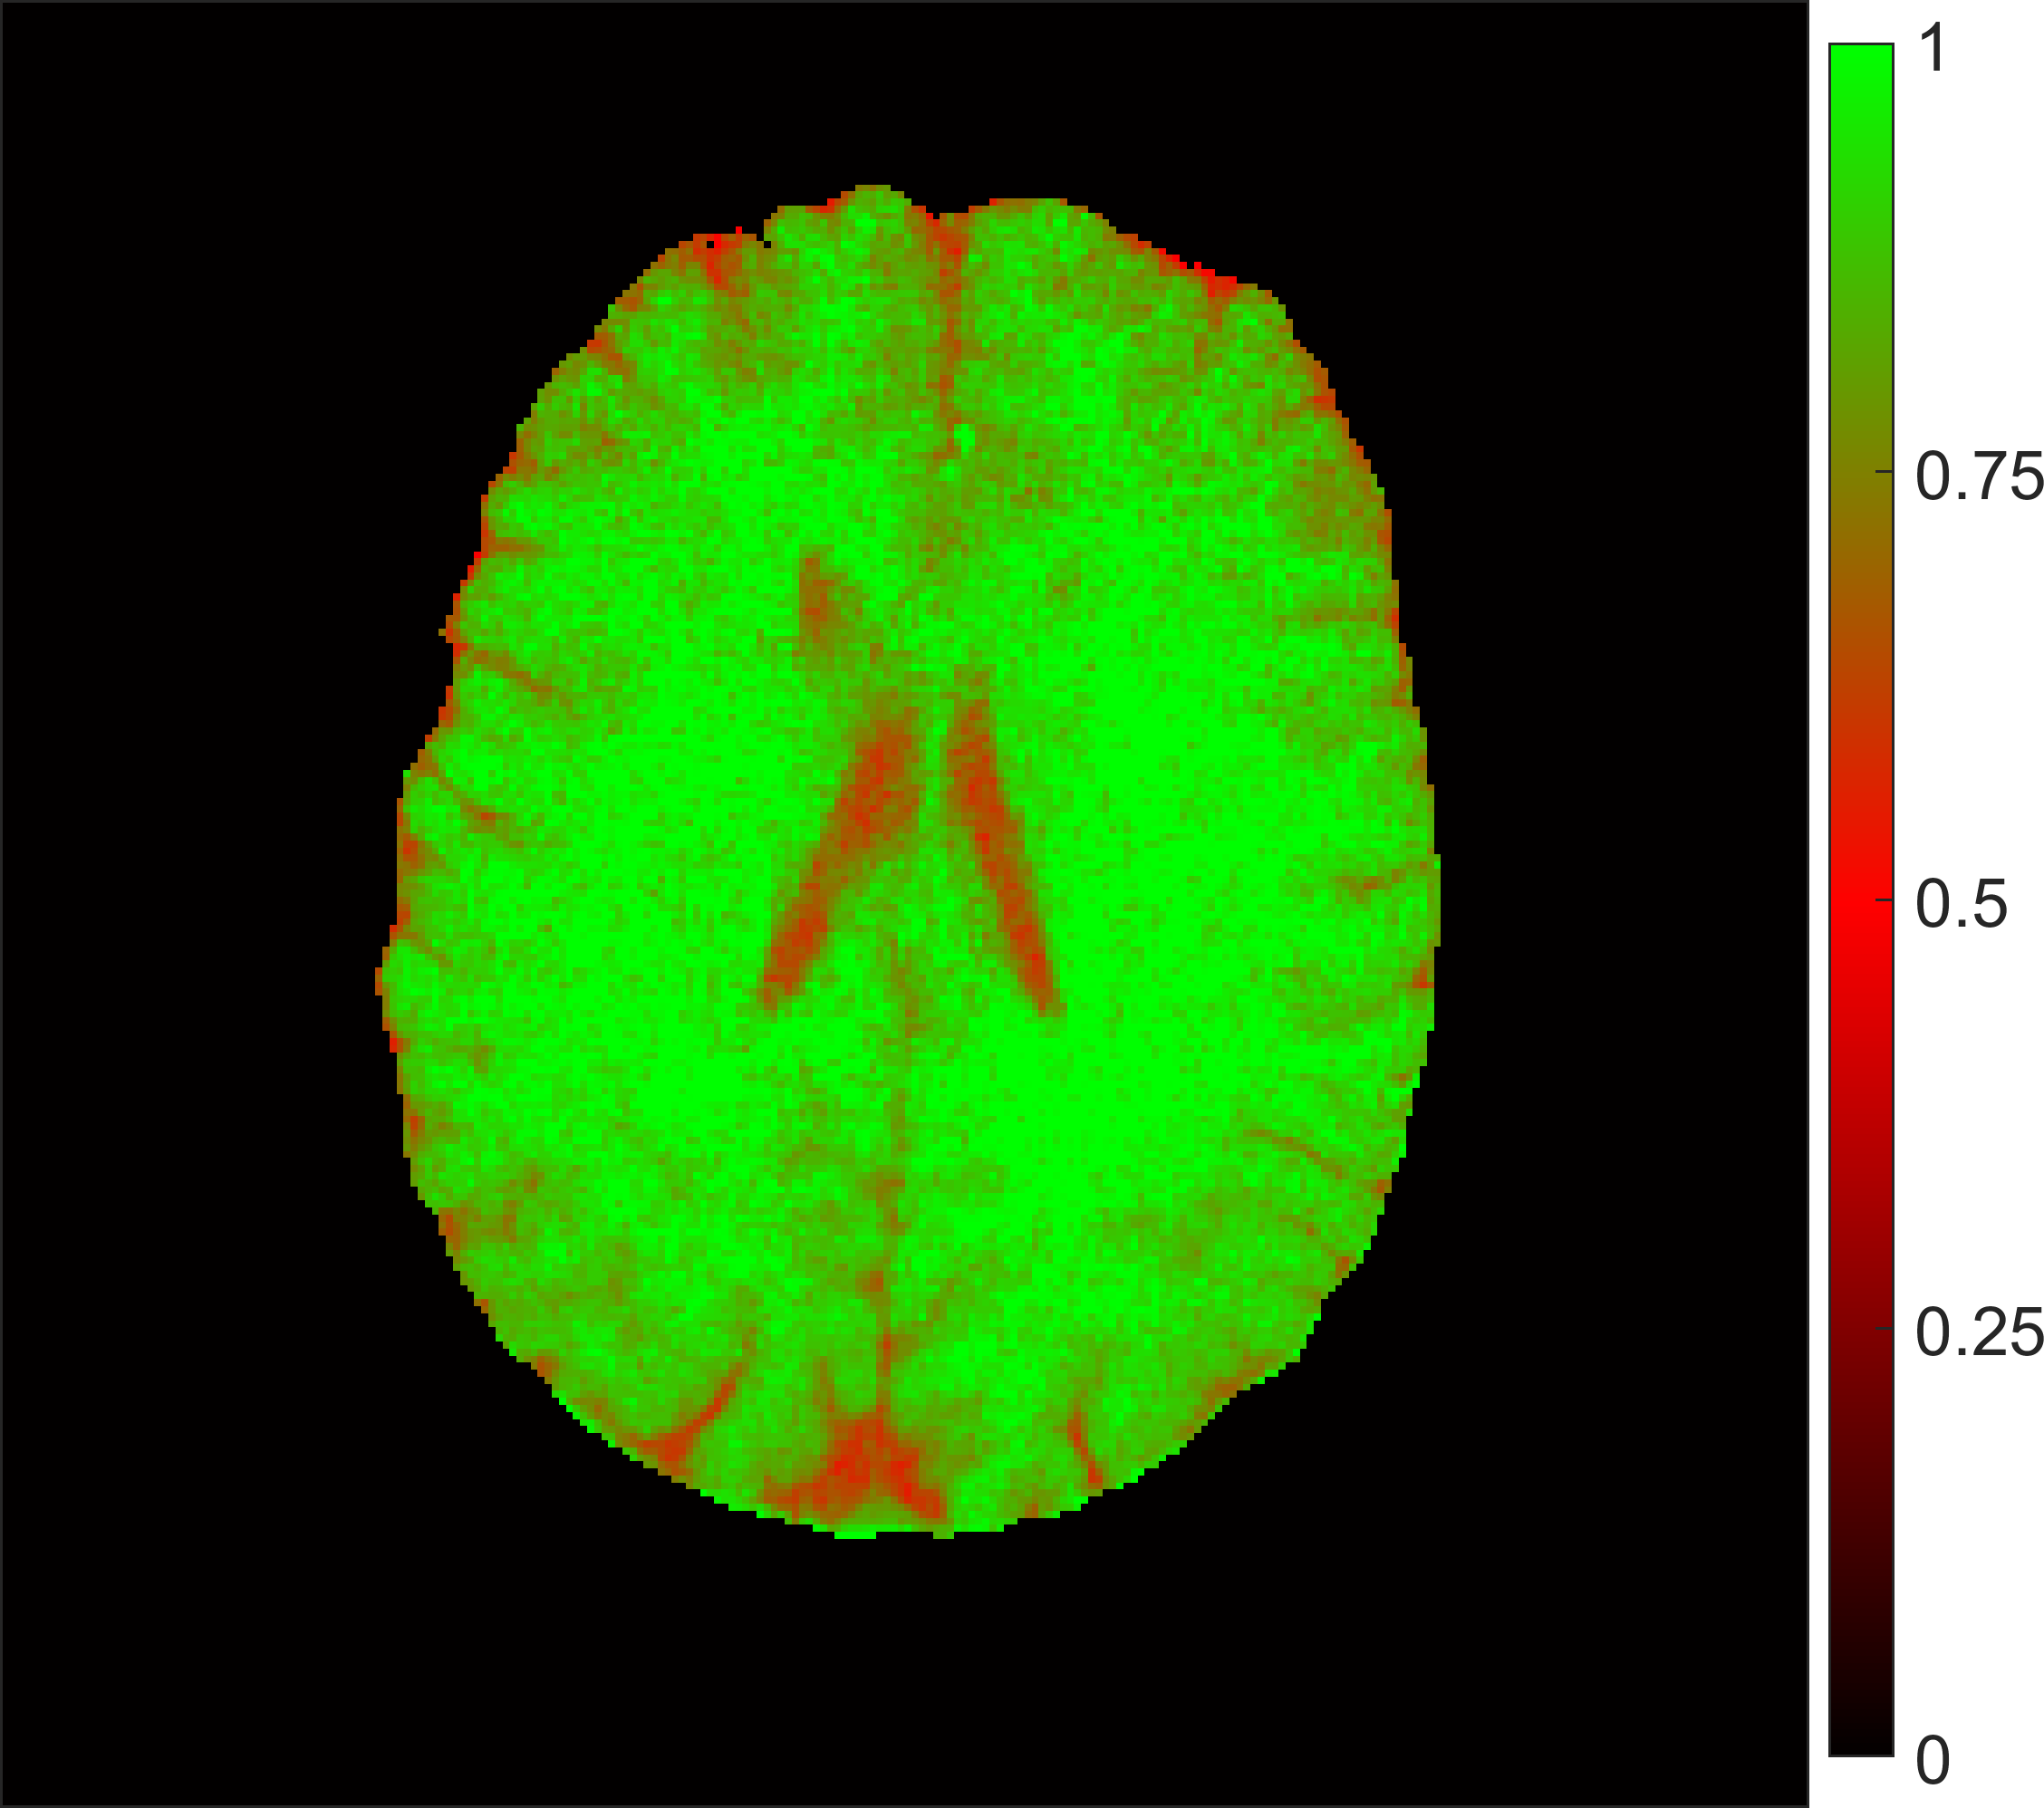

The efficiency of the inversion preparation is shown in Figure 4. Clearly, 100% inversion was not achieved in tissues with long relaxation time, but worked fine in other areas.

Figure 4: Inversion efficiency as determined of the ratio between the two parameters for M0 in the combined fit. Complete inversion was not achieved in tissues with long relaxation time, but worked fine in other areas.